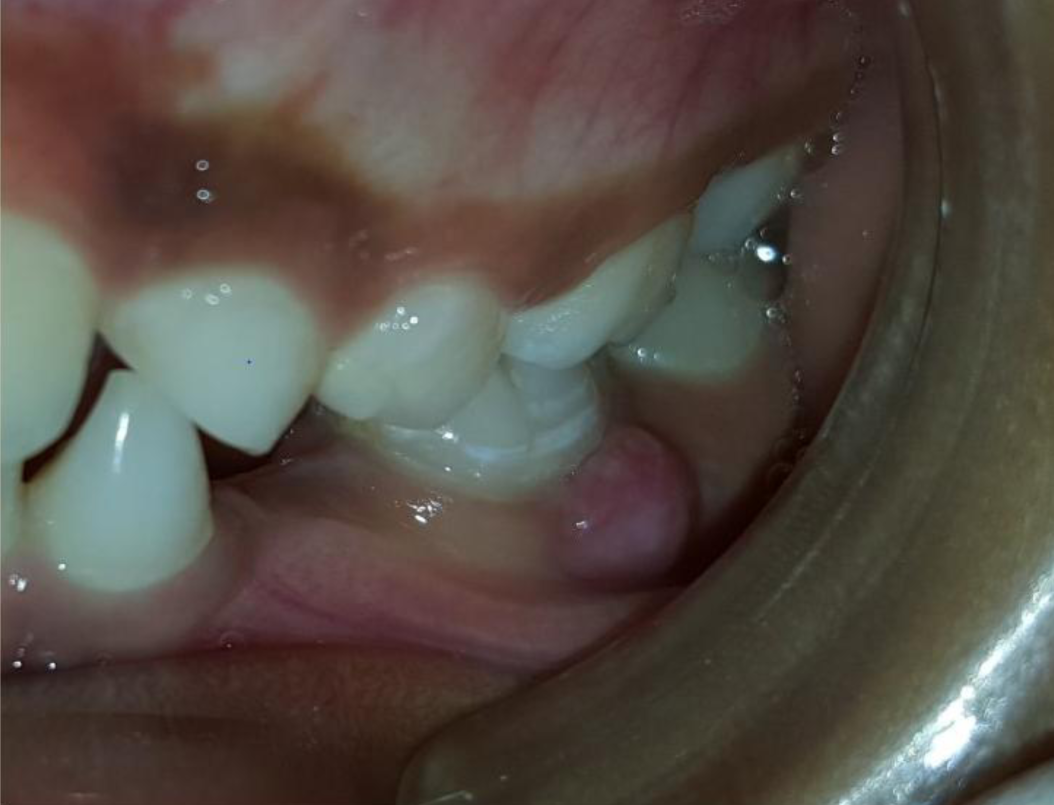

A nine year old boy reported to the Department of Pedodontics and Preventive Dentistry of Bharati Vidyapeeth Deemed University, Sangli with a chief complaint of pain and abscess in the lower left back region of the jaw since one month. Patient was a known case of autism spectrum disorder. He was inattentive, hyperactive and showed repetition of gestures. Psychological testing report showed childhood autism rating scale (CARS) 2, which falls into mild to moderate autistic category. Vineland social maturity scale (VSMS) measuring the social intelligence of child was found to be 31.5 with social age of around 5-6years. The family history was non-contributory. He was not on any medications and had reported no history of drug allergies. Extra-oral examination showed no specific findings (Figure 1). Intraoral examination revealed multiple carious lesions (Figure 2) (Figure 3). Occlusal caries involving enamel, dentin and pulp with 55 and 75. Intra oral dentoalveolar abscess was also seen in relation with 75 (Figure 4). Dentinal caries was seen with 85 and occlusal pit and fissure caries was seen with 65. No soft tissue abnormalities were appreciated. Radiographic evaluation by orthopantomogram was also done which revealed no abnormality (Figure 5). It was difficult for the patient to co-operate on the dental chair and understand the instructions given to him; hence treatment was planned under general anaesthesia. A complete pre anaesthetic evaluation was done and the patient was categorized under ASA II. Treatment plan was explained to the child’s parents and a written consent was obtained from them. The dental treatment done under general anaesthesia included pulpectomy of 55, 75 with glass ionomer cement restoration followed by placement of pre trimmed and pre contoured stainless steel crowns (Figure 6) (Figure 7). Glass ionomer cement restorations were done in 65 and 85 and pit and fissure sealants application on 16, 26, 36 and 46. Post-operative orthopantomogram showed well placed restorations and crowns (Figure 8). Patient’s post-operative recovery was uneventful. Treatment rendered reduced the pain and discomfort.Oral hygiene care instructions were given to the parents and maintenance protocol was explained and they were also encouraged for regular follow-up for preventive dental care. The two months follow-up revealed improved eating habits of the child.

Figure 4 Intra-oral dentoalveolar abscess in 75 region.